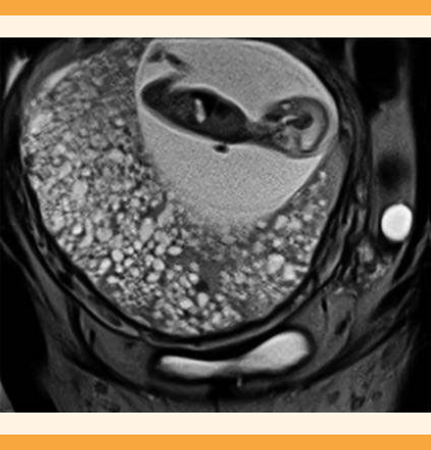

La resonancia magnética confirmó el diagnóstico y se encontró un feto dentro del saco amniótico (Figura 2) y se identificaron los bordes de las placentas, que se encontraron por separado; una de ellas con formación de quistes hidrópicos. Figura 3

Figura 2 Resonancia magnética, corte coronal, donde se observan dos placentas. Una con aumento de tamaño y características hidrópicas y la otra con feto vivo dentro del saco amniótico.

En el ultrasonido de las 11 a 14 semanas de gestación (Figura 1) se observó un embarazo gemelar bicorial, con imágenes anecoicas de característica quística, con alta sospecha de embarazo gemelar, con feto vivo de 11.3 semanas y mola hidatiforme. En la resonancia magnética (Figuras 2 y 3) se observó la invasión corial a los tejidos aledaños, la caracterización y la delimitación del embarazo molar, que se apreció solo un componente quístico, con ausencia de partes fetales; esto explicó el aumento del tamaño del útero, que fue superior al esperado para las semanas de embarazo, con crecimiento y evolución rápida, característica de esta anomalía del embarazo.